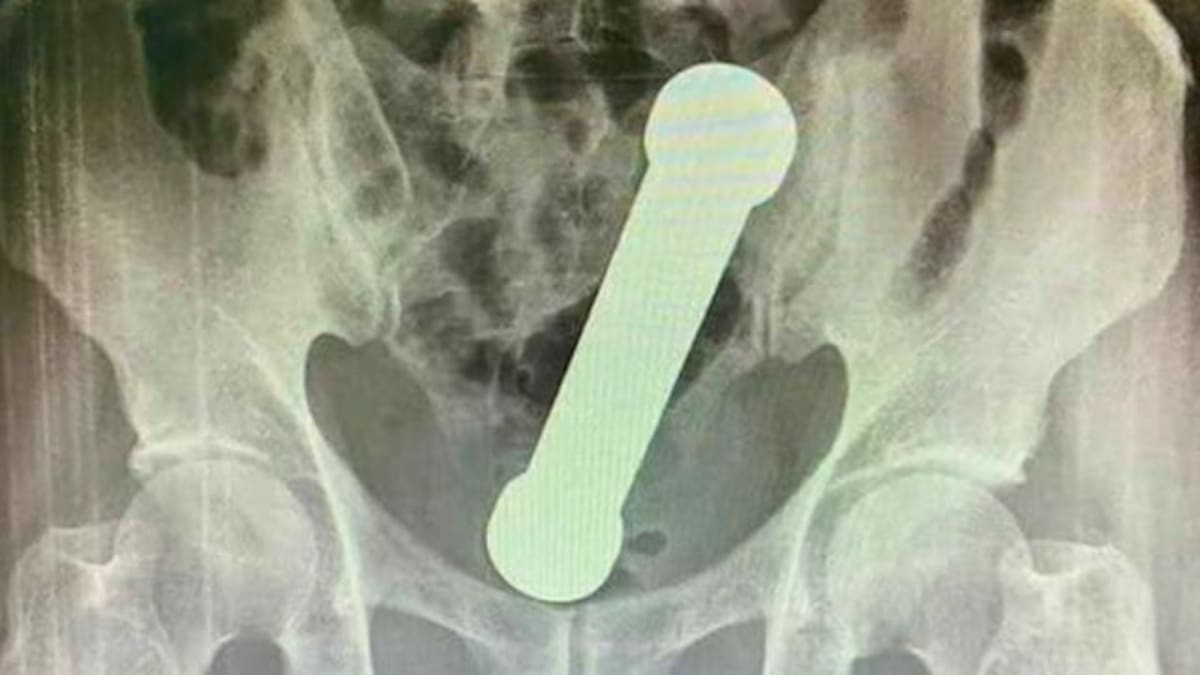

Un hombre dejó sorprendidos a los médicos luego de que le encontraran el objeto incrustado en su intestino.